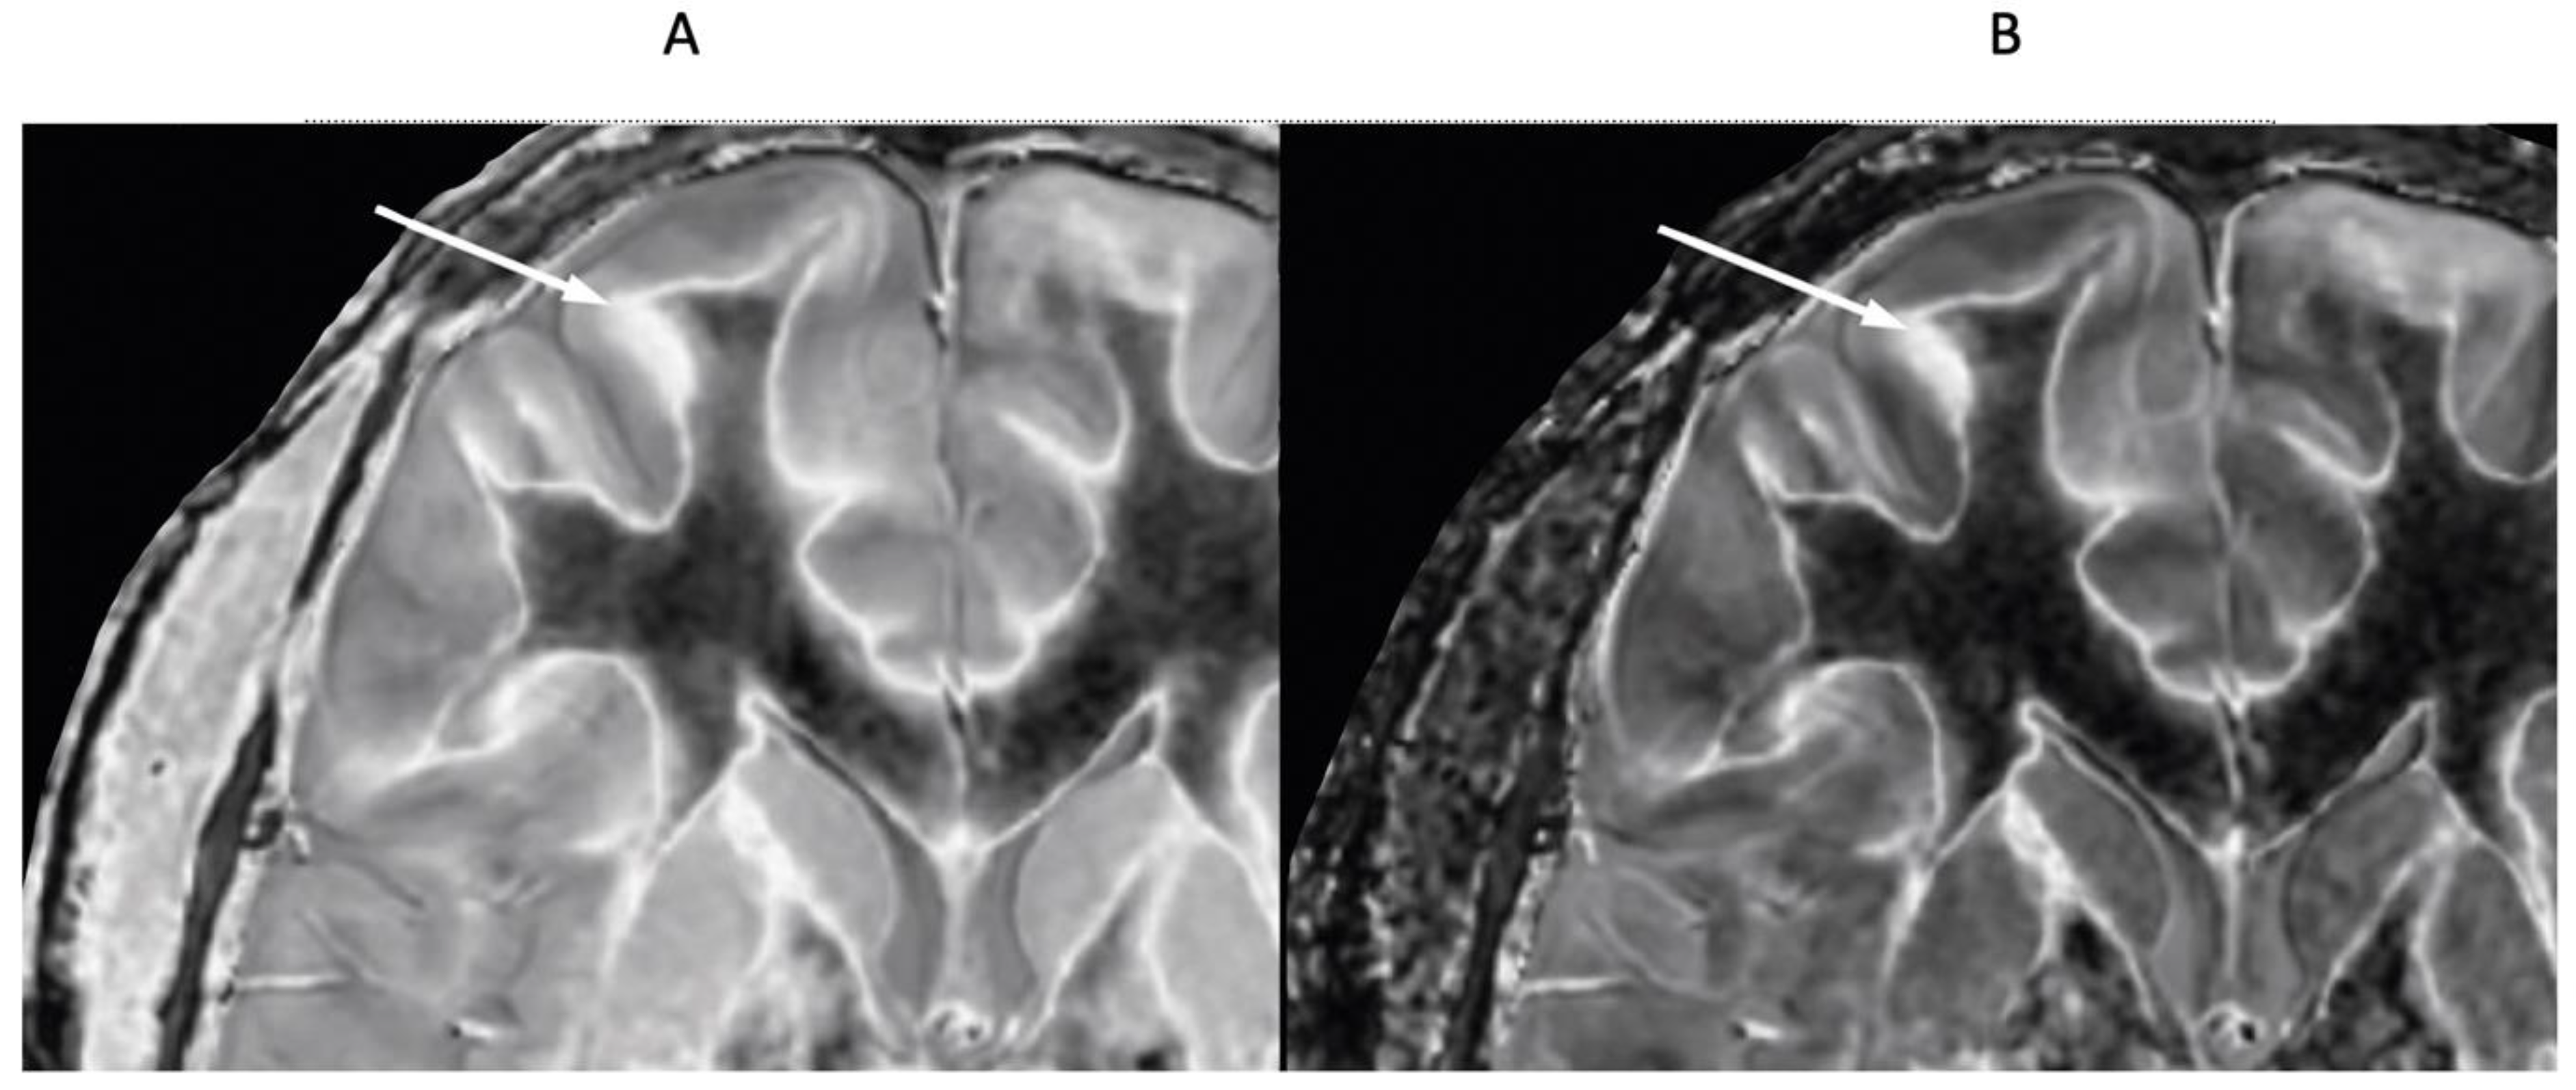

Figure 13 shows a leucocortical lesion in a 41-year-old female patient with MS in remission. The lesion appears blurred and relatively featureless on the narrow mD dSIR image (Figure 13A), but shows a disrupted boundary within the lesion on the lSIR image (Figure 13B). Figure 13C shows dSIR (blue) and lSIR (orange) signal profiles across the lesion. These are plots of signal vs. distance in mms on the image. The lSIR profile has higher signal and generally steeper slopes than the dSIR profile, corresponding to the graphs in Figure 4.

Figure 13.

Forty-one-year-old female patient with MS. A leucocortical lesion is shown in the right medial frontal lobe on the narrow mD dSIR image (A) and the matching synthetic lSIR image (B) (arrows). There are also left to right profiles with signal plotted against position (in mm) for the dSIR (blue) and lSIR (orange) images (C) at the level of the horizontal arrows shown in (A,B). No boundary between white matter and gray matter is seen within the lesion in (A). A disrupted high signal boundary between white matter and gray matter is seen in the lesion in (B). The lSIR profile (orange) has higher signal and generally steeper slopes than the dSIR profile (blue) in (C). The difference in signal (or contrast) achieved for the same change in position is generally greater with the lSIR filter.

Figure 14 shows another leucocortical lesion in a 24-year-old female patient with MS in remission. dSIR (Figure 14A) and cdSIR (Figure 14B) images are compared. The cdSIR image shows higher contrast. In addition, the frontal white matter has a more uniform low signal intensity on the cdSIR image. These are features consistent with the graphs in Figure 5A.

Figure 14.

Twenty-four-year-old female patient with MS in remission (TIs = 350 ms, TIi = 500 ms). Narrow mD dSIR (A) and composite (T1 and T2) cdSIR (TIs/TEs = 350/7 and 80 ms; TIi/TEi = 500/7 ms) (B) images. A leucocortical lesion is seen on the dSIR image (A) and with higher contrast on the cdSIR image (B) (arrows). White matter and gray matter boundaries show higher contrast and are narrower on the composite filter cdSIR image (B). Also, white matter is more uniformly low signal in (B). These features are consistent with the attenuation of the first IR TIs filter signal increasing contrast and narrowing boundaries at the positive pole and decreasing these at the negative pole as shown in Figure 5A.